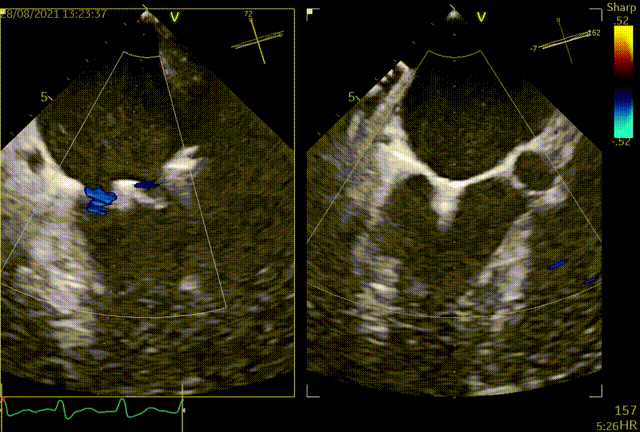

术前超声评估:

术前TEE提示重度功能性二尖瓣返流,返流位于A2/P2;

前瓣长度:22mm;后瓣长度:12mm;

前、后瓣叶对合深度:10mm;对合长度4mm;

瓣叶及瓣环无钙化,二尖瓣有效开口面积6.0cm²。

术前TEE提示二尖瓣重度返流,返流位置位于A2/P2区